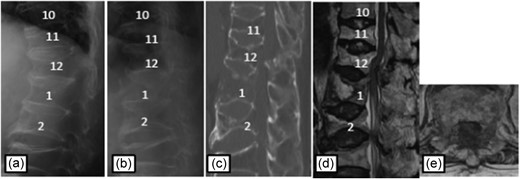

Plain radiographs on initial assessment (a) and on admission (b); Sagittal CT image (c) showing the hyperextension fracture at T12; MRI T2-weighted image (d, e) showing the epidural hematoma compressing the dura matter.